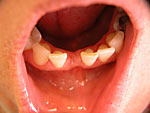

Frontzahn-Implantation: